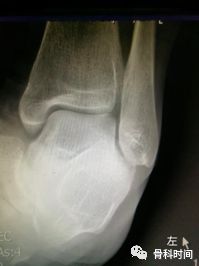

30 岁青年女性,1 年前右踝首次发生崴脚,未行外固定,伤后右踝间断数次崴脚,双侧踝关节应力正位片测量距骨倾斜角,左侧为 0°,右侧 7°,右侧虽尚不能诊断踝关节不稳,但距骨倾斜角增大,对比对侧仍考虑为崴脚后未外固定所致。